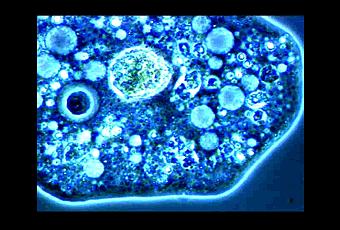

Las bacterias modificadas tienen en sus membranas unas proteínas a modo de jeringuilla con las que son capaces de inyectar cualquier proteína que quepa por su poro. En el caso de usar anticuerpos, estos se unirían dentro de la célula a sus antígenos. Debido a su capacidad de inhibir a las enzimas, pueden modificar la actividad celular por lo que, aparte de su función diagnóstica, podrían llegar a usarse como terapia contra enfermedades de tipo inflamatorio o cancerígeno del tracto gastrointestinal o urinario. Una de las principales ventajas de este sistema es que al estar vivas, las bacterias producen continuamente los anticuerpos y no hay que aplicar varias dosis. Por ejemplo la inyección de los anticuerpos de E. coli no conlleva ni la invasión de las células por parte de las bacterias ni la transferencia de su material genético. El Centro Nacional de Biotecnología de España, han obtenido una patente en los Estados Unidos que les permite utilizar bacterias no patógenas como si de jeringuillas microscópicas se trataran.